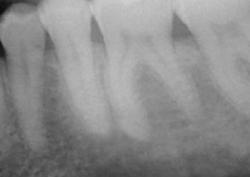

Зуб удаляют не только при сильной боли. Иногда пациент почти не предъявляет жалоб, но на рентгеновском снимке видно воспаление у корня, трещину, разрушение ниже десны или риск осложнений для соседних зубов. В таких ситуациях врач предлагает удаление как безопасный выход и заранее объясняет, какие варианты восстановления подойдут после заживления.

Метод выбирают по рентгеновскому снимку и осмотру. Врач учитывает форму корней, объем разрушения, состояние кости и мягких тканей. В практике применяются:

Без диагностики качественно удалить зуб сложно. В КДС перед вмешательством врач проводит осмотр, оценивает состояние десны, соседних зубов и прикуса. Далее выполняют рентгеновский снимок, чтобы увидеть корни, форму каналов, состояние кости и возможные воспалительные изменения.

Диагностика помогает выбрать тактику и снизить риск осложнений. Врач заранее понимает, потребуется ли разделение корней, наложение швов, дополнительная обработка лунки, а также прогнозирует сроки заживления.